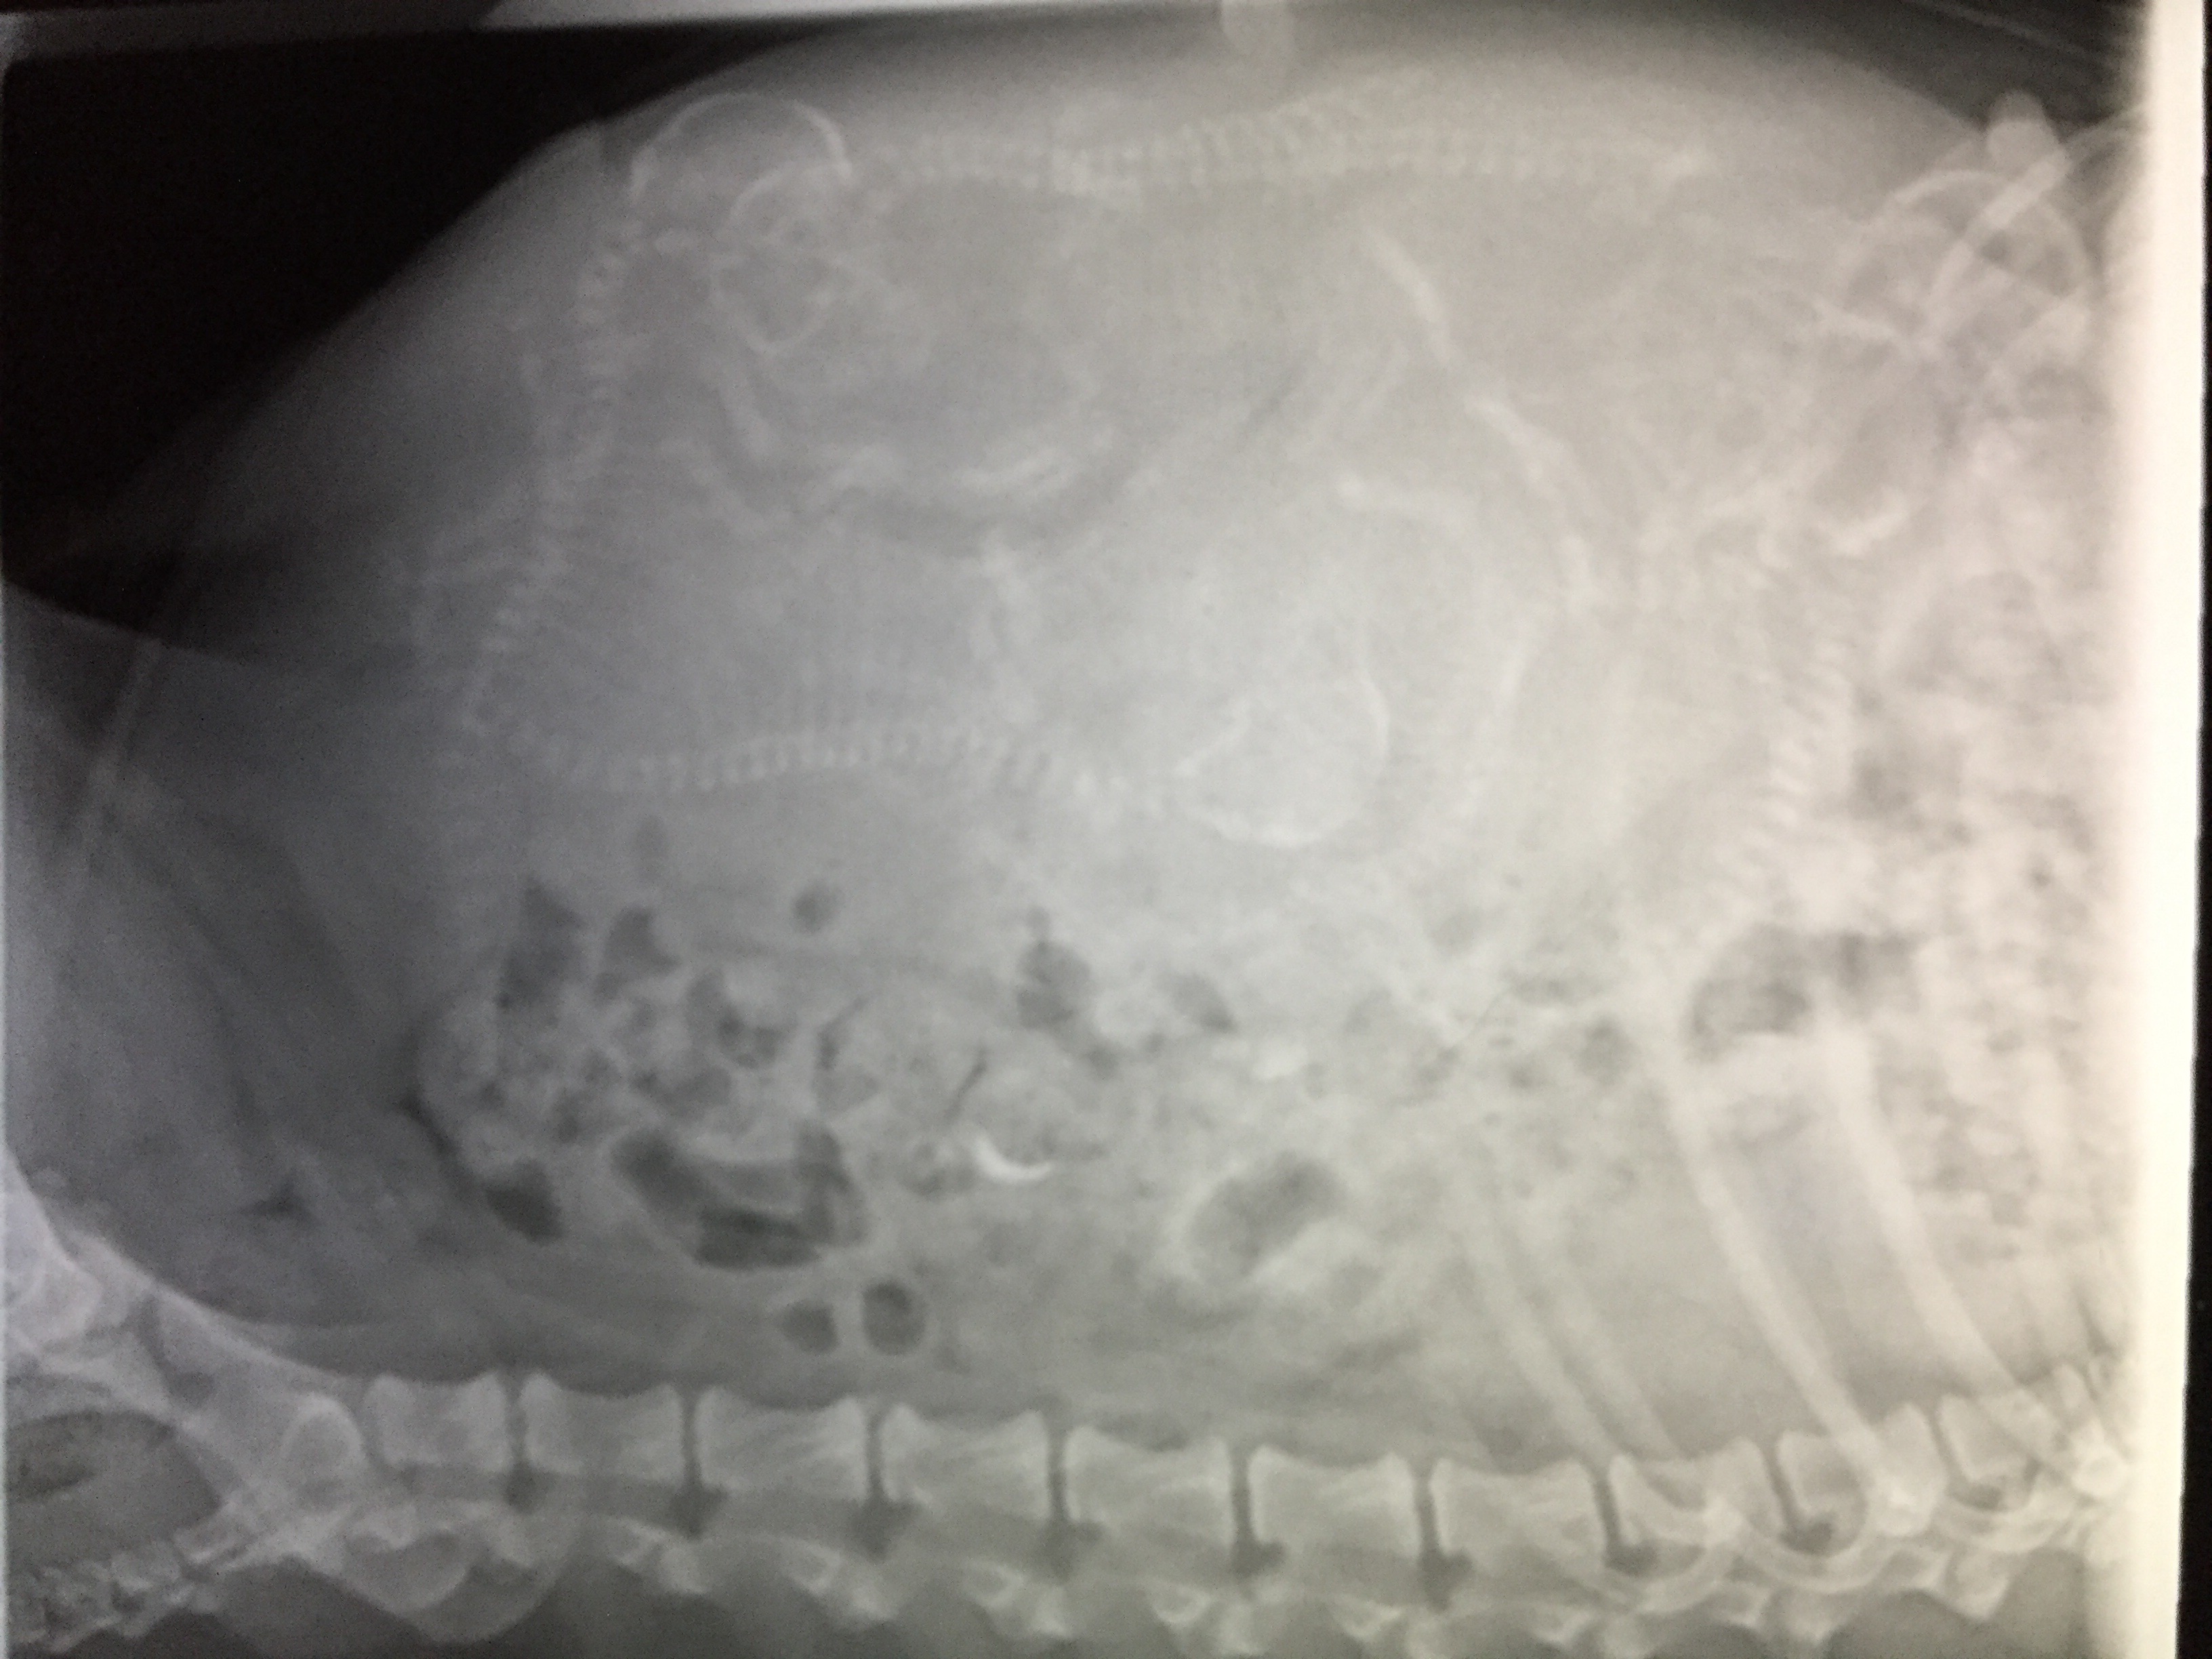

Perry and Sparkle puppies are on there way…

Puppies are coming… Feb 2017

Published on February 5, 2017 by lloyjennifer

Perry & Sparkle : Feb, 2017

GCH CH Premiere’s Rock Your World RA JH NAP NJP NFP “Perry”

CH Emery’s In It To Win It “Sparkle”